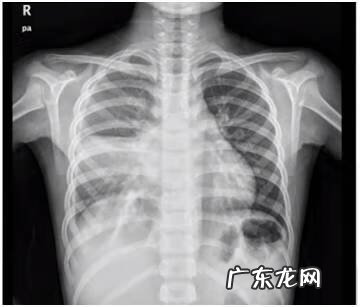

治疗前:

文章插图

图示右肺感染,右侧肺叶外带弧形高密度影,提示胸腔积液、夜间积液的可能

胸部CT:右肺感染,右下肺为著,右侧胸腔液,左侧胸膜局部稍增厚